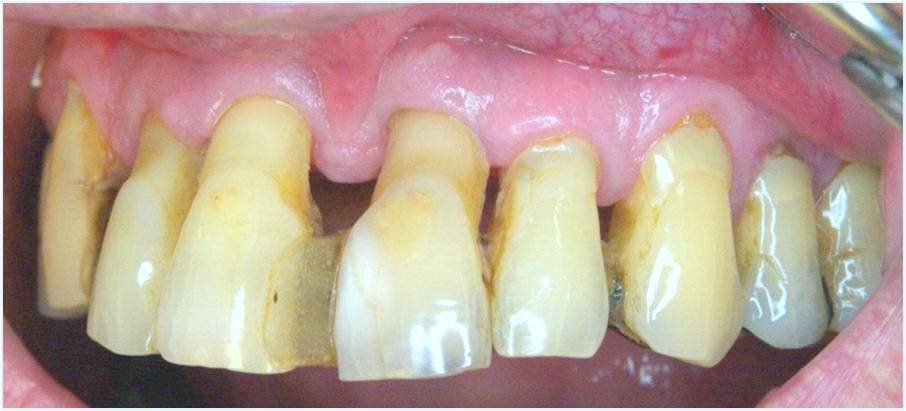

На фото представлены все этапы имплантации зубов от исходного состояния пациента до конечного результата.

На фото обычный случай замены одного зуба имплантатом, а также решение в случае беззубой челюсти или челюсти, пораженной пародонтозом.

Имплантация в стоматологии «Аркобалено» при пародонтозе зубов, представлены все этапы имплантации под ключ.